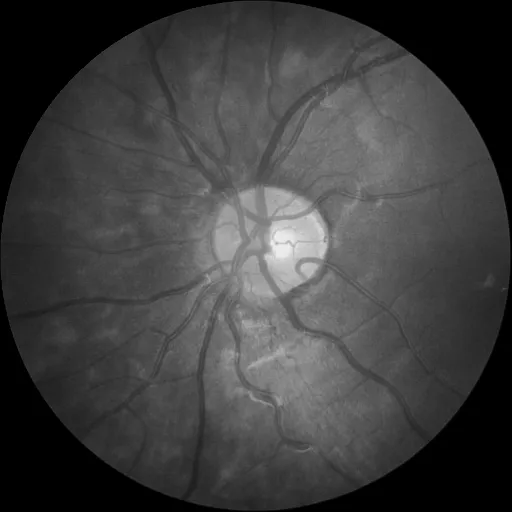

| 预测图像 | 分割图像 |

|---|---|

![]() | ![]() |